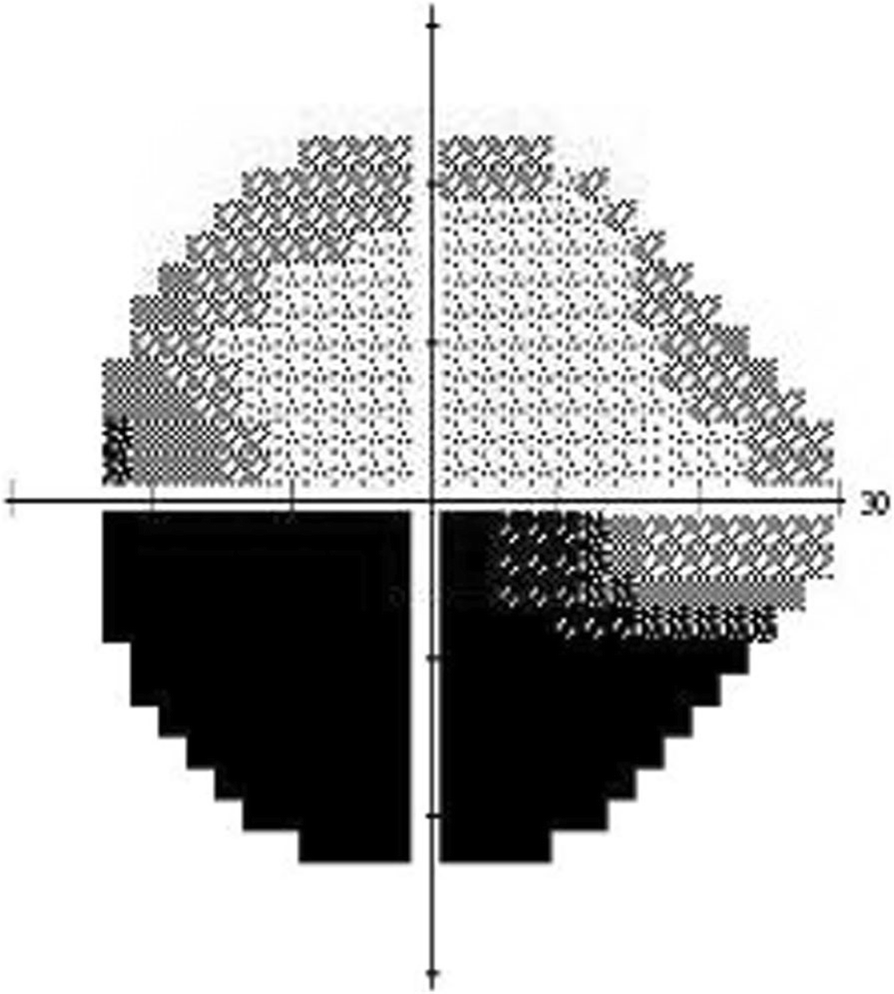

Fig. 1From: Characterization of retinal microvasculature in acute non-arteritic anterior ischemic optic neuropathy using the retinal functional imager: a prospective case seriesInferior altitudinal visual field defectBack to article page